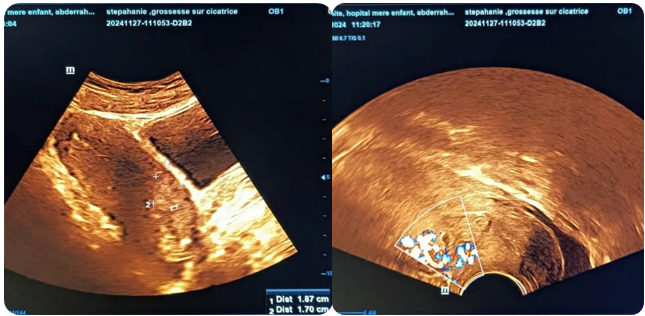

• Pelvic ultrasound (09/09/2024): (figure 1)

• The uterus is enlarged, measuring 11.5x53x72 mm

• Seat of a 33 mm supra-isthmic ovarian sac, hypotonic, containing an embryo with no active movement or cardiac activity.

• Monoembryonic intrauterine pregnancy arrested at 07 weeks amenorrhea and 03 days

• Associated moderate corporal intracavitary hematometry measuring 43x14mm

Figure 1: Isthmic Gestational Sac Containing an Embryo with no Cardiac Activity